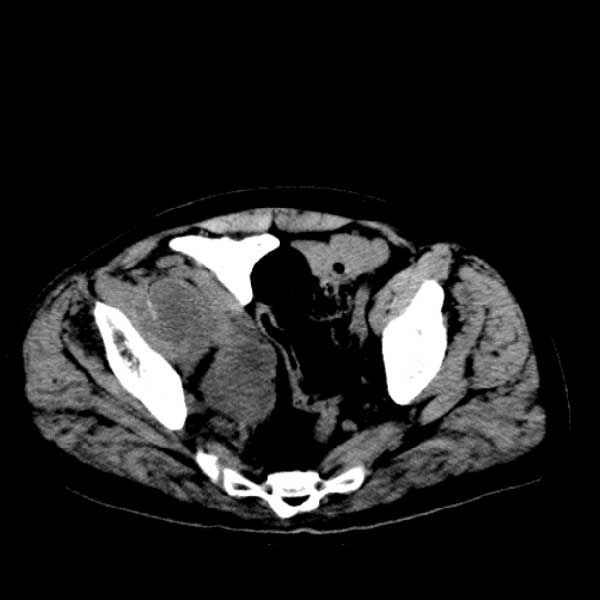

标题: CT13513:男 71 腹部疼痛20余天,近几天高热就诊,骨窗未见异 [打印本页]

标题: CT13513:男 71 腹部疼痛20余天,近几天高热就诊,骨窗未见异

考虑感染性病变可能性大,起源于阑尾?

感染,脓肿形成

考虑为化脓性阑尾炎.脓肿形成.及多肌肉累及.

考虑右侧腰大肌脓肿,向右髂窝、右腹股沟流注。

支持化脓性阑尾炎伴右髂窝脓肿、腰大肌腰方肌脓肿形成。

考虑腹腔及盆腔化脓性炎症,累及右侧髋关节及腹股沟区.

首先考虑化脓性阑尾炎伴腰大肌、腰方肌脓肿,不除外回盲部结核。

回盲部癌待排除。

患者肠镜检查考虑结肠癌,病理证实

患者肠镜检查考虑结肠癌,病理证实。肺部ct可见多发结节,考虑转移